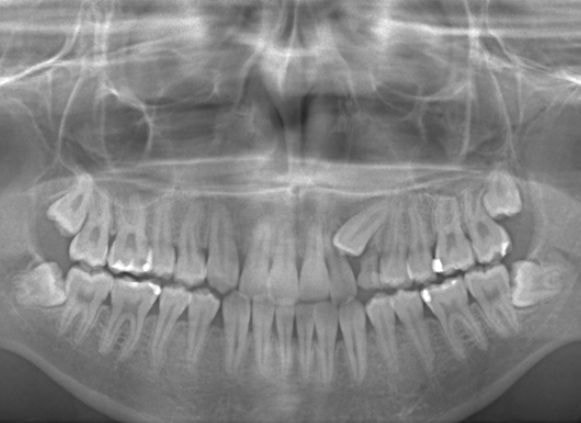

やはり統計通り、左上3番の埋伏です。

左上2番の歯根吸収が認められますが、保存不可能なレベルではありません。

成人の反対咬合なので、少し顎関節にダメージはありますが、重症ではありません。

治療中のレントゲンです。

7番、8番の状態や歯根のパラレリング(平行性)をチェックしています。

左上2番の歯根の状態もなんとかもちそうです。

上顎劣成長症例ですが、鼻腔の状態も悪くありません。